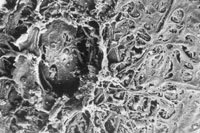

ALT uses a blue-green laser to create thermal burns in the trabecular meshwork (TM). This laser uses a relatively small spot size (about 50nm) of varying intensity to photocoagulate the TM (see image on page 63). It's a non-selective laser that creates crater-like depressions and transfers thermal energy to nearby TM structures. The collateral damage caused to all surrounding tissues results in the rupture of trabecular beams and collagen supporting structures, scattered debris and fibrosis (see image at left). ALT is thought to reduce IOP by mechanical and/or biologic mechanisms. The mechanical theory is based on the idea that the laser burns cause the TM to contract in the area of the burn and the structures adjacent to the TM to widen, allowing for increased outflow. The biologic theory involves the recruitment of macrophages and the increased phagocytic activity of trabecular cells.

| Scanning electron microscopy of ALT treatment. |